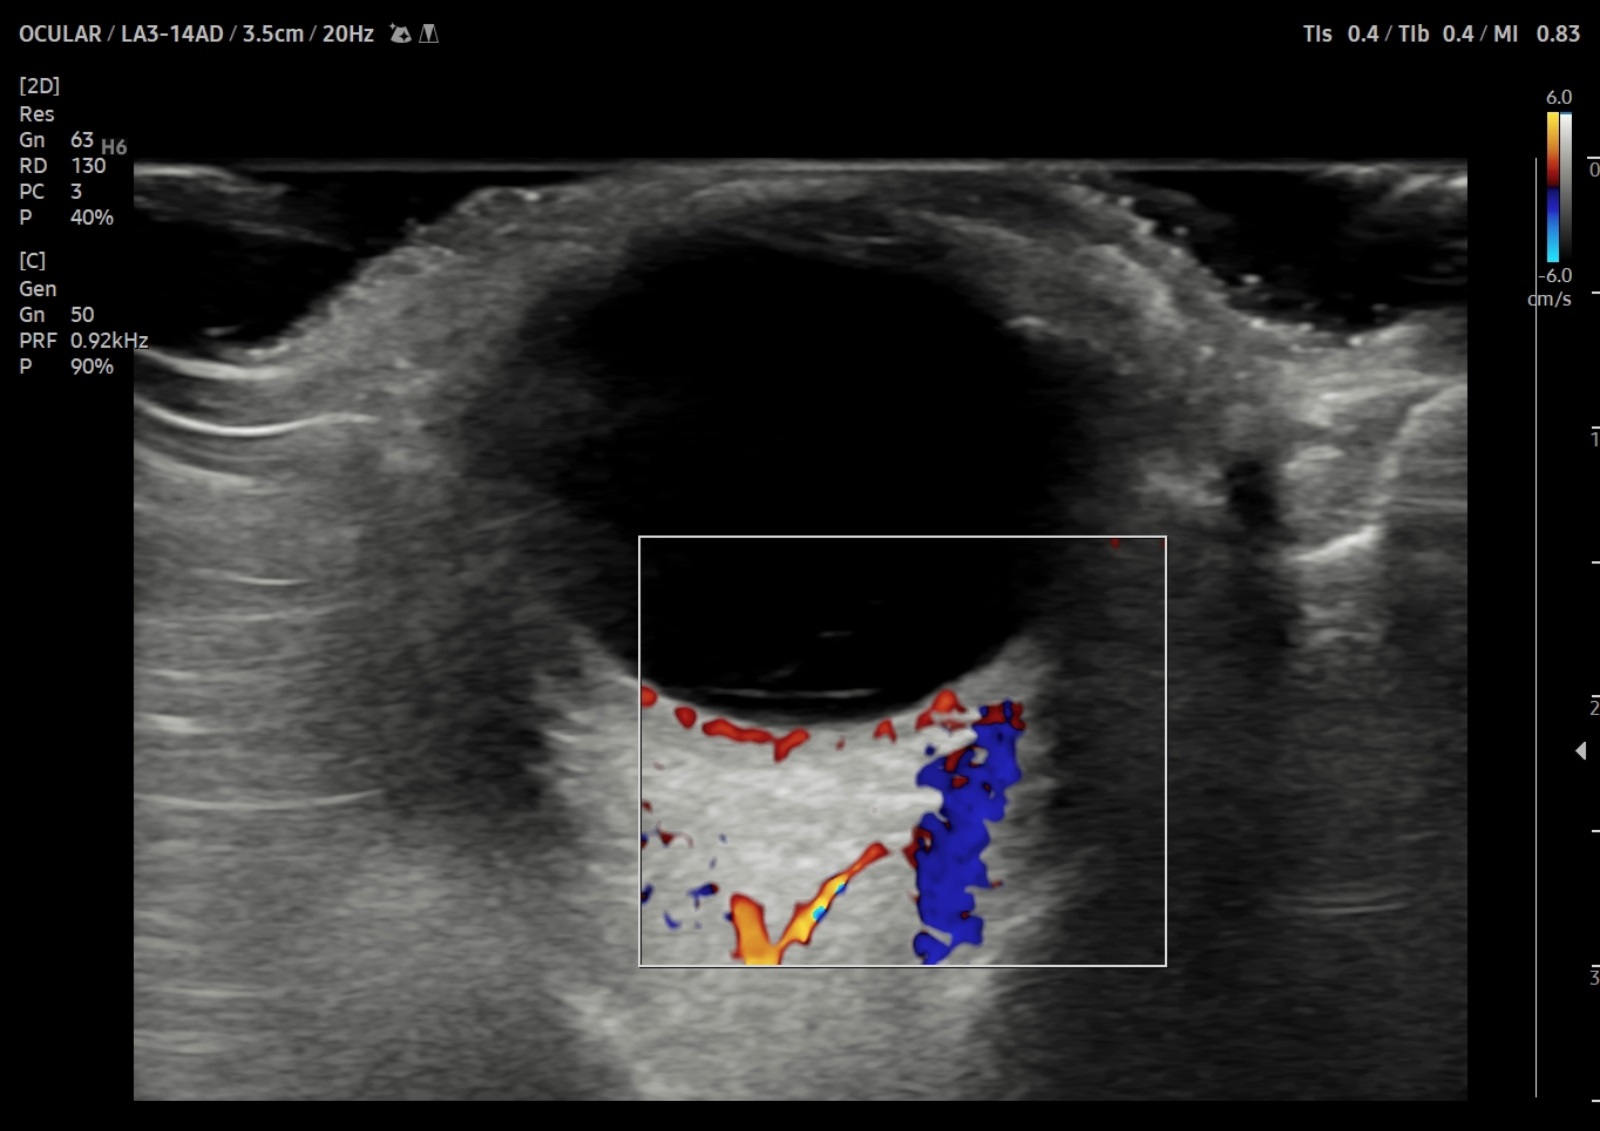

La ecografía ocular clínica en consulta, sonda lineal apoyando la sonda sin presionar, ojo cerrado, abundante gel, reducción de la potencia manteniendo atención al índice térmico y mecánico. Mostró una lámina hiperecogénica móvil en polo posterior, no originada en el nervio óptico (cuya distancia de vaina del nervio óptico menor de 5 mm), con bamboleo marcado a la maniobra dinámica (signo de la 'lavadora') y abundantes ecos móviles difusos en vítreo (aportaré video de maniobra dinámica).

El desprendimiento de vítreo posterior (DVP) suele mostrar una membrana hiperecogénica fina, libre. El desprendimiento de retina (DR) que nace de la papila en forma de "V" hacia periferia. En cambio, en el desprendimiento de retina regmatógeno (DRR), la lámina puede no nacer de papila, anclaje bilateral y movimiento ondulante y acompañado de hemorragia vítrea, como se evidenció.

Se confirma el diagnóstico de desprendimiento de retina regmatógeno con hemorragia vítrea en la 2.ª visita a Oftalmología y se indicó cirugía urgente.